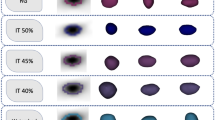

The selective and iterative method for performance level estimation (SIMPLE) algorithm for label fusion was modified with a weight map given by an expert that indicates the importance of each region in the evaluation of segmentation results. Voxel-based weights specified by an expert when performing the label fusion step in atlas-based segmentation were introduced into the modified SIMPLE algorithm. These weights incorporate expert knowledge on accuracy requirements in different regions of a segmentation. Using this knowledge, segmentation accuracy in regions known to be important can be improved by sacrificing segmentation accuracy in less important regions. Contextual information such as the presence of vulnerable tissue is then used in the segmentation process. This method using weight maps to fine-tune the result of multi-atlas-based segmentation was tested using a set of 146 atlas images consisting of an MR image of the lower abdomen and a prostate segmentation. Each image served as a target in a set of leave-one-out experiments. These experiments were repeated for a weight map derived from the clinical practice in our hospital.

The segmentation accuracy increased 6 % in regions that border vulnerable tissue using expert-specified voxel-based weight maps. This was achieved at the cost of a 4 % decrease in accuracy in less clinically relevant regions.